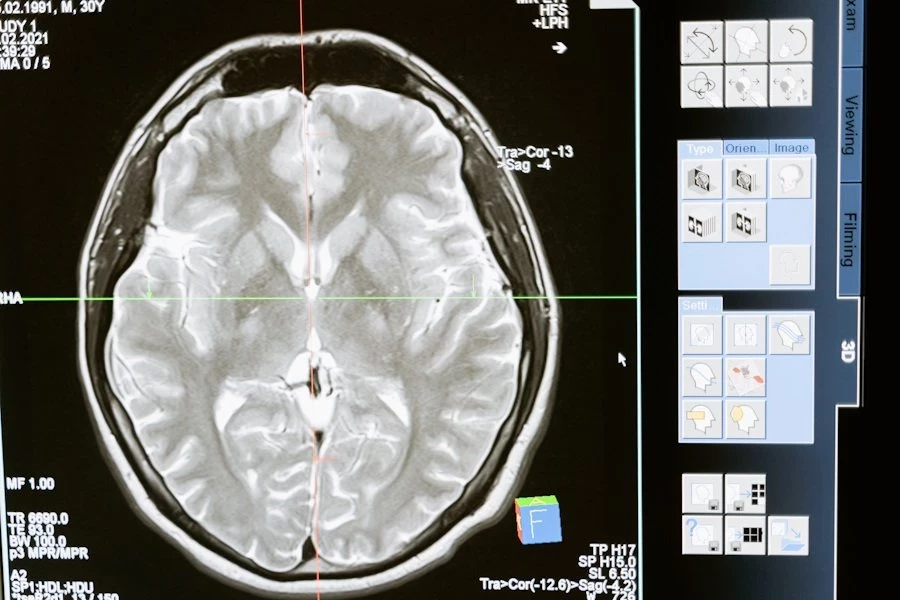

Ученые из University of Pennsylvania (США) выяснили, что мужчины и женщины по-разному реагируют на полную анестезию, и это связано с физиологическими особенностями организма. Исследование, опубликованное в Neuroscience, показало, что женщины возвращаются в сознание после наркоза значительно быстрее, чем мужчины.

В эксперименте приняли участие 30 здоровых добровольцев обоих полов в возрасте от 22 до 40 лет. Испытуемым вводили изофлуран — популярный ингаляционный анестетик, используемый во всем мире. Ученые следили за изменениями мозговой активности с помощью электроэнцефалографии (ЭЭГ), фиксируя показатели как во время действия наркоза, так и после его завершения.